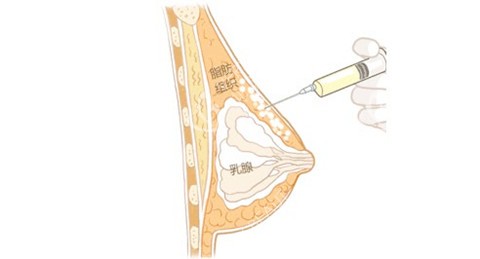

他自创的“脂肪三维护活体系”,从提取、提纯到填充全程把控:取脂时用2.0mm超细钝针,配合“扇形低负压抽取”,减少脂肪细胞破损;提纯时采用“离心+过滤+静置”三重处理,去除油脂、血水等杂质,保留活性高的脂肪颗粒;

填充时用“多点、分层、微量”注射法,将脂肪均匀注入乳腺后间隙和皮下层,避免堆积形成结节,不少求美者反馈术后3个月成活率高,基本一次就能达到理想罩杯。